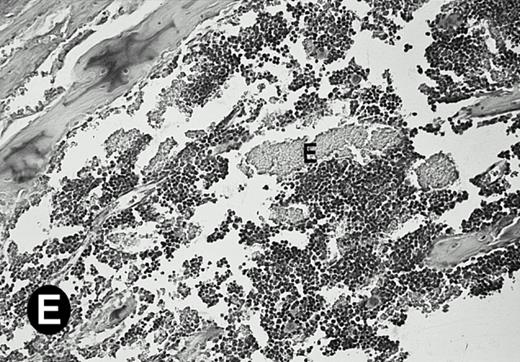

Because around and after birth, the spleen together with the bone marrow become the major hematopoietic organs in mice, we examined P4.2 expression in these hematopoietic organs by in situ hybridization of tissue sections, as described above. In newborn mice, P4.2-specific labeling was detected in specific areas of the spleen (data not shown). Significant P4.2 expression was seen in the emerging red pulp, which later makes up the largest part of the organ and is the center for erythropoiesis and megakaryocyte production. As the components of the spleen become more distinguished, increasing P4.2 hybridization signal was still confined to the red pulp on postnatal day 7 and day 15 (Fig6A and B). No P4.2-specific labeling was seen in the white pulp, which consists of germinal centers for lymphocytes, plasma cells, and macrophages. In older animals, P4.2 expression remains localized exclusively in the red pulps (data not shown). Upon higher magnification of areas containing red pulps from spleen sections of 15-day-old mice, P4.2-specific labeling was detected in erythroid cells, particularly at higher intensity in areas with more mature erythroid cells (lightly stained by crystal violet; Fig 6C and D). In contrast, P4.2 hybridization signal was not detected in megakaryocytes (easily identified as giant cells with a polylobulated nucleus surrounded by a large cytoplasm; Fig 6C and D). Histologic identification of all these cell types was confirmed by standard hematoxylin-eosin staining of adjacent tissue sections.

P4.2 gene expression in the mouse spleen and bone marrow. Shown are in situ hybridization analysis of serial spleen sections from a 15-day-old mouse (A through D) using the P4.2 antisense riboprobe. A representative region of red pulp (RP) or white pulp (WP) in the spleen is indicated in (A) and (B). Higher-power views of a red pulp region are shown in (C) and (D). The lightly stained areas (labeled with “E”) enrich more mature erythroid cells and show substantial P4.2 hybridization. Arrowheads indicate isolated megakaryocytes. Sections containing bone marrows from a 7-day-old mouse (E and F) were also hybridized with the P4.2 antisense riboprobe. A representative erythroid colony in the bone marrow is labeled with “E.” Micrographs were taken with a 20× (A and B) or 40× (C through F) objective. (A, C, and E) Bright-field illumination; (B, D, and F) dark-field illumination.

To examine what types of cells in bone marrows expressed P4.2 transcripts, we conducted in situ hybridization of bone marrow sections from mice at various times after birth. Similar to that observed in the spleen, P4.2-specific labeling was detected only in erythroid cells and colonies in the bone marrow from 7-day-old mice (Fig 6E and F). Similar results were obtained in bone marrow of older animals (data not shown). In addition, no P4.2 hybridization signal was seen in cells of nonerythroid lineage, including megakaryocytes. These results indicate that P4.2 message was specifically expressed in cells of the erythroid lineage in postnatal hematopoietic organs.